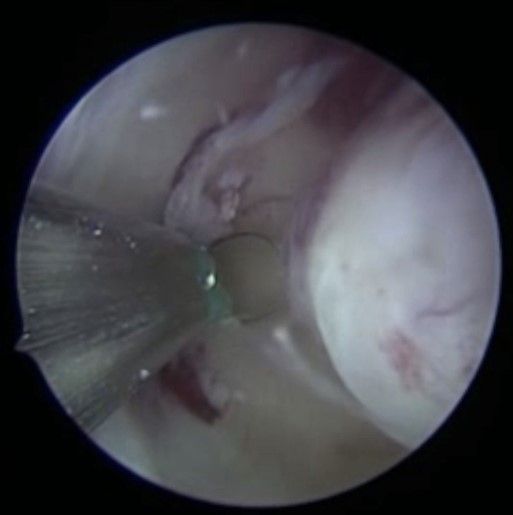

Bei der Gebärmutterspiegelung wird die Gebärmutterhöhle mit Kochsalzlösung aufgedehnt. Eine Kamera mit integrierter Elektroschlinge wird in die Gebärmutter eingeführt. Die vorhandenen Myome können nun schrittweise unter Sicht abgetragen werden. Mittels modernsten Ultraschalluntersuchungen werden die Myome während der Operation noch einmal genau dargestellt. Bei sehr großen Befunden können zwei Operation zur kompletten Myomentfernung notwendig sein.

Abb. 4: Sicht auf eine submuköses Myom (unter der Gebärmutterschleimhaut) per Gebärmutterspiegelung